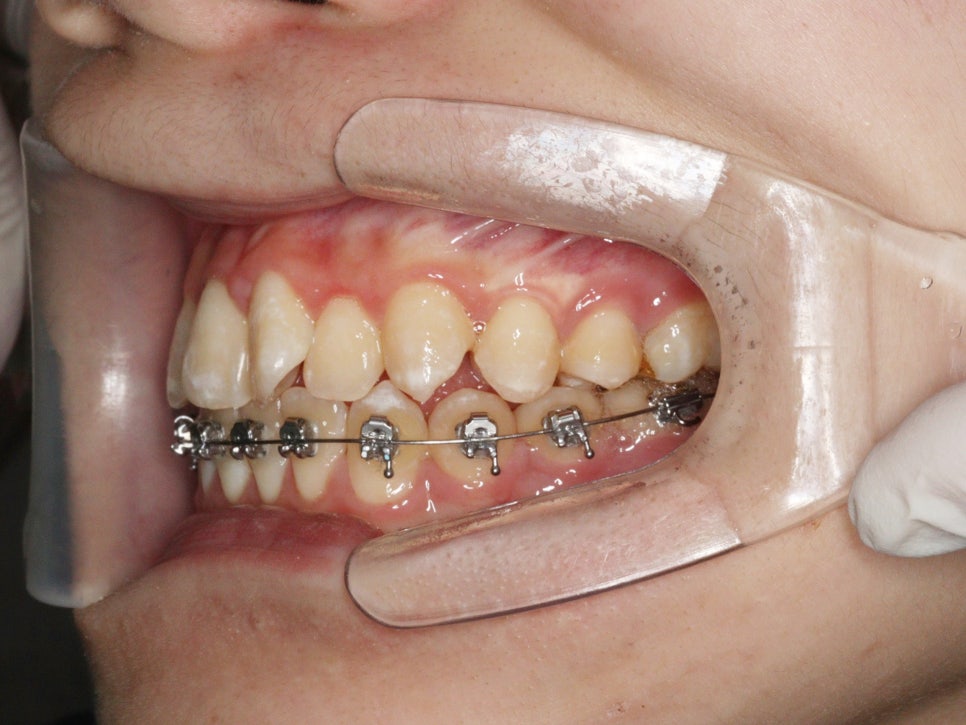

위와 같이 삐뚤삐뚤했던 치열을 가진 아이가 와서 #철사교정 치료를 하고

마무리가 되었습니다.

이 아이는 치료를 위해 #악궁확장 장치도 4개월간 사용하였습니다.

악궁확장장치의 사용까지 필요했던 아이로, 전체 치료기간이 조금 긴 느낌입니다.

2022.4.26. ~ 2024.5.27.

약 2년1개월이 소요되었네요

스마일이 훨씬 자연스러워져 보입니다.